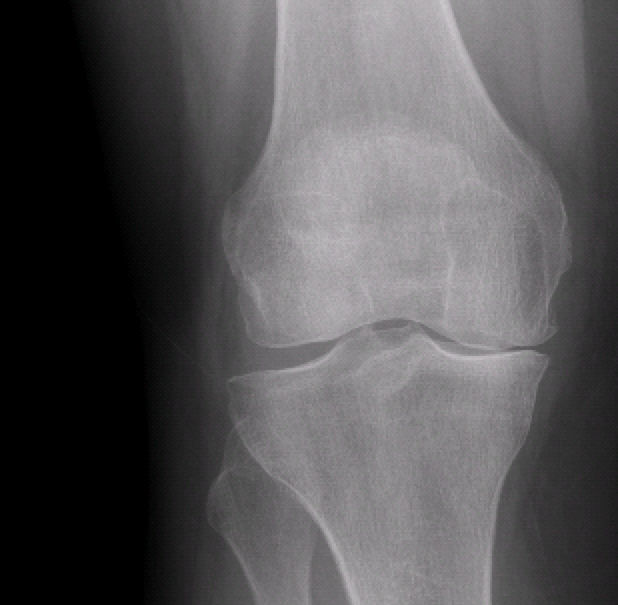

Kısmi (unikondiler, parsiyel) diz protezi uygulaması sırasında dizin sadece aşınmış olan yüzeyleri değiştirilir. Kısmi diz protezleri, sıklıkla dizin iç yarısı için uygulanır ama dış yarısı ve diz kapağının altında da başarı ile uygulanırlar (Resim 1). Dizin tamamının aşınmış olduğu durumlar ve ilerleyici romatoid artrit (iltihaplı romatizma), ankilozan spondilit gibi hastalıklarda kısmi protezler uygun değildir. Dizin sadece aşınmış olan kısımlarına yüzey kaplaması yapılır ve sağlam taraftaki menisküs, eklem kıkırdağı ve bütün diz bağları korunur. Bu da total (tam) diz protezine kıyasla daha normal bir diz hissi, daha kolay ameliyat sonrası iyileşme ve daha iyi eklem hareket açıklığı elde edilmesini sağlar. Hastaların günlük yaşam veya işe dönmeleri çok daha kısa sürede gerçekleşir. Robotik kısmi diz protezleri ile dizin aşınma öncesi sağlıklı durumu, büyük bir doğruluk ve yumuşak doku dengesi sağlanacak şekilde oluşturulur. Robotik cerrahi önce kısmi diz protezleri ile başlamış ve sonrasında total diz ve kalça sistemleri geliştirilmiştir. Bu nedenle dünyada en fazla ve uzun süre takipli deneyim kısmi protezlerledir.

Resim 1: Dizin sadece iç yarısı aşınmış olan bu hasta kısmi (unikondiler) protez için uygun.